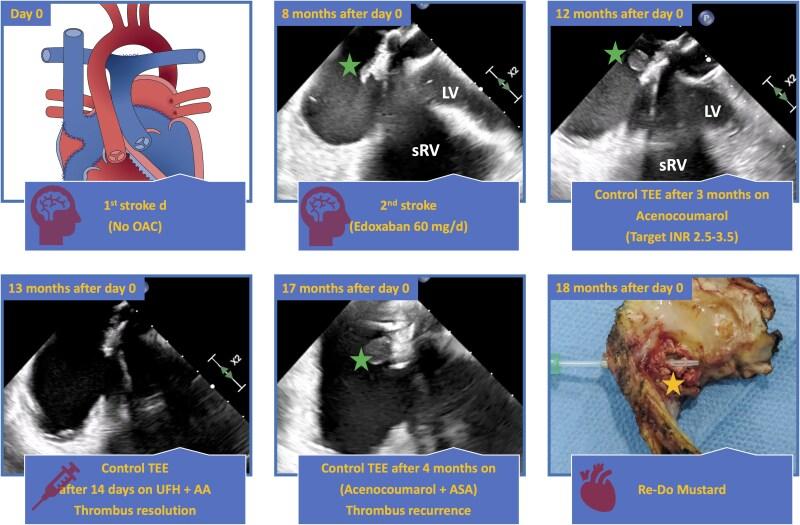

We describe the case of a 43-year-old Caucasian male with recurrent cardioembolic strokes due to a calcified, broken, and thrombosed baffle with floaty, anticoagulant-resistant thrombi adhered to the side of the pulmonary venous return of Mustard patch. Surgery was the only curative option due to thrombi recurrence under different regimes of anticoagulation.

A case of recurrent cardioembolic strokes long after Mustard surgery due to thrombi on a heavily calcified pericardial patch is presented. A fracture in the patch led to the exposure of thrombogenic material, which had accumulated around the pacemaker (PM) leads on the systemic venous side of the baffle. This exposure allowed thrombotic material to reach the pulmonary venous side, ultimately entering the subaortic right ventricle and the systemic circulation. In the Mustard procedure, the material used for the baffle construction is prone to degeneration and calcification over time. We hypothesize that chronic mechanical stress from the PM leads might have contributed to the gradual erosion and fracture and consequently thrombosis of the heavily calcified patch, leading to recurrent strokes. Surgery became necessary as aggressive anticoagulation failed to prevent thrombus recurrence.

本文报告了一例Mustard手术后很久因严重钙化的心包补片上的血栓导致反复心源性栓塞性卒中的病例。补片骨折导致血栓形成物质暴露,这些物质积聚在挡板体静脉侧的起搏器(PM)导线周围。这种暴露使血栓形成物质到达肺静脉侧,最终进入主动脉下右心室和体循环。在Mustard手术中,用于构建挡板的材料随着时间的推移容易发生变性和钙化。我们推测,PM导线产生的慢性机械应力可能导致了严重钙化补片的逐渐侵蚀、骨折,进而导致血栓形成,引发反复卒中。由于积极抗凝未能预防血栓复发,手术成为必要手段。